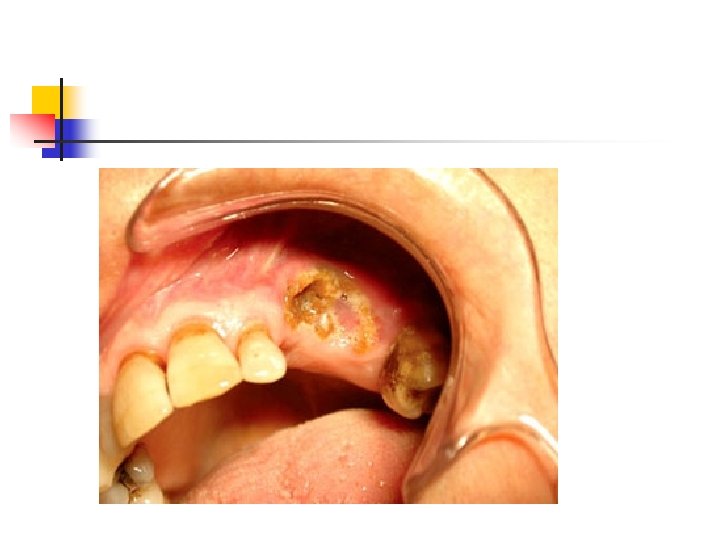

AKUT LÖSEMİLER Klinik Özellikler (4) Ekstramedüller infiltrasyon bulguları: Lenfadenopati Splenomegali Hepatomegali Dişeti hipertrofisi Deri infiltrasyonu Granülositik sarkom…. .

AKUT MYELOMONOSİTİK LÖSEMİ M 4 • %15 -25 • Myeloid ve monositik komponent ≥ % 20 • Periferik kanda monositoz, promonositler, • Ekstramedüller infiltrasyon sık • Dişeti hipertrofisi

Dikkat n n n Dişeti hipertrofisi Kanama diyatezi Gerekirse hemogram bakısı Konsültasyon istemi Remisyonda olan hastanın dental girişimlerini hızla tamamlama